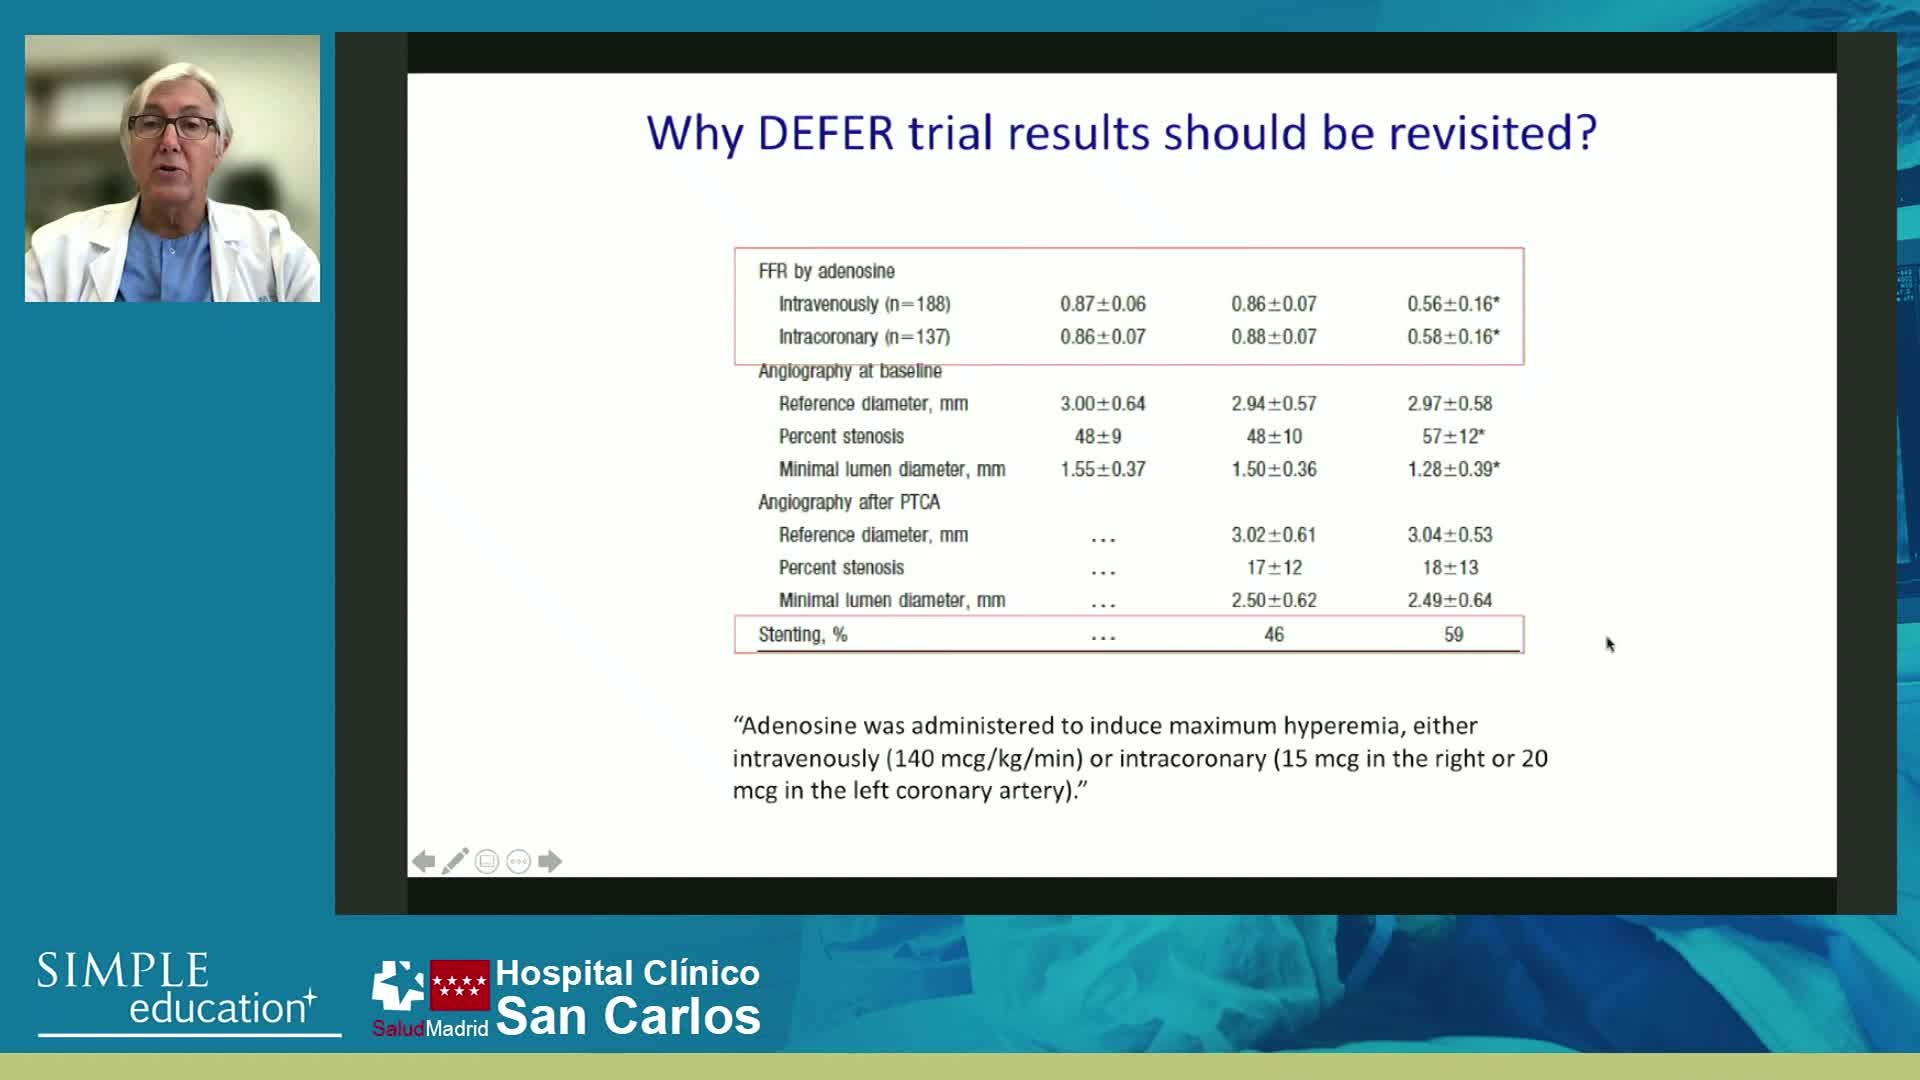

Welcome & Applied coronary physiology to plan and guide PCI-2023 EAPCI Consensus